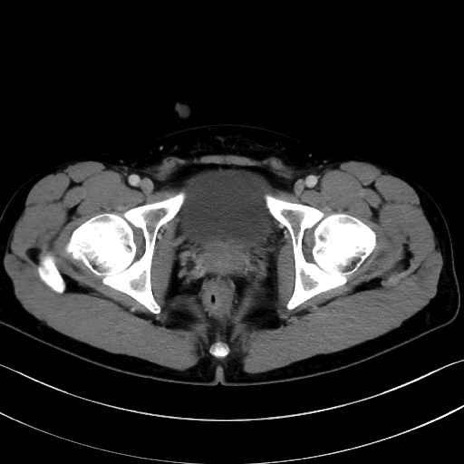

3. 殿部の筋肉(表層・中層・深層)

大殿筋 (Gluteus maximus)

中殿筋 (Gluteus medius)

小殿筋 (Gluteus minimus)

大腿筋膜張筋 (Tensor fasciae latae)

4. 深層外旋六筋(股関節の深部)

梨状筋 (Piriformis)

内閉鎖筋 (Obturator internus)

外閉鎖筋 (Obturator externus)

大腿方形筋 (Quadratus femoris)